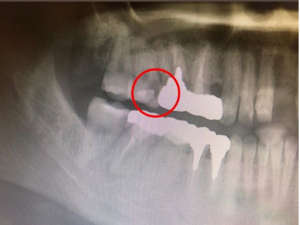

そしてまず、これが現在の直接的な問題点。

ここの赤丸のところがすごく虫歯になっていそうです。。。

そして、特筆すべきは先ほど紹介した、エックス線画像である。

凄いことに歯科医師が治療を進める事に、どんどんシャクレ(受け口)になっていった。